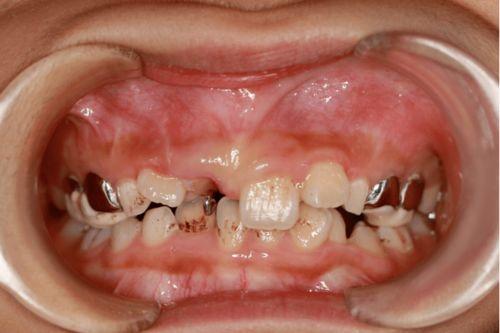

一、齲齒(蛀牙)

當(dāng)口腔中的細(xì)菌與食物殘?jiān)嗷プ饔?,產(chǎn)生酸性物質(zhì),這些酸性物質(zhì)會(huì)逐漸侵蝕牙齒的琺瑯質(zhì),形成齲洞。

長(zhǎng)期口腔衛(wèi)生不良,食物殘?jiān)谘揽p和牙齒表面堆積,為細(xì)菌滋生提供了有利環(huán)境。

據(jù)統(tǒng)計(jì),全球約60%-90%的學(xué)齡兒童和近100%的成年人都有齲齒問題。

癥狀和危害

早期齲齒可能沒有明顯癥狀,但隨著齲洞加深,會(huì)出現(xiàn)牙齒敏感、疼痛,尤其在進(jìn)食冷熱酸甜食物時(shí)。

如果不及時(shí)治療,齲齒會(huì)進(jìn)一步破壞牙髓,導(dǎo)致牙髓炎、根尖周炎,甚至牙齒脫落。

嚴(yán)重的齲齒還可能影響咀嚼功能,導(dǎo)致消化問題,并且與心血管疾病、糖尿病等全身性疾病存在一定關(guān)聯(lián)。